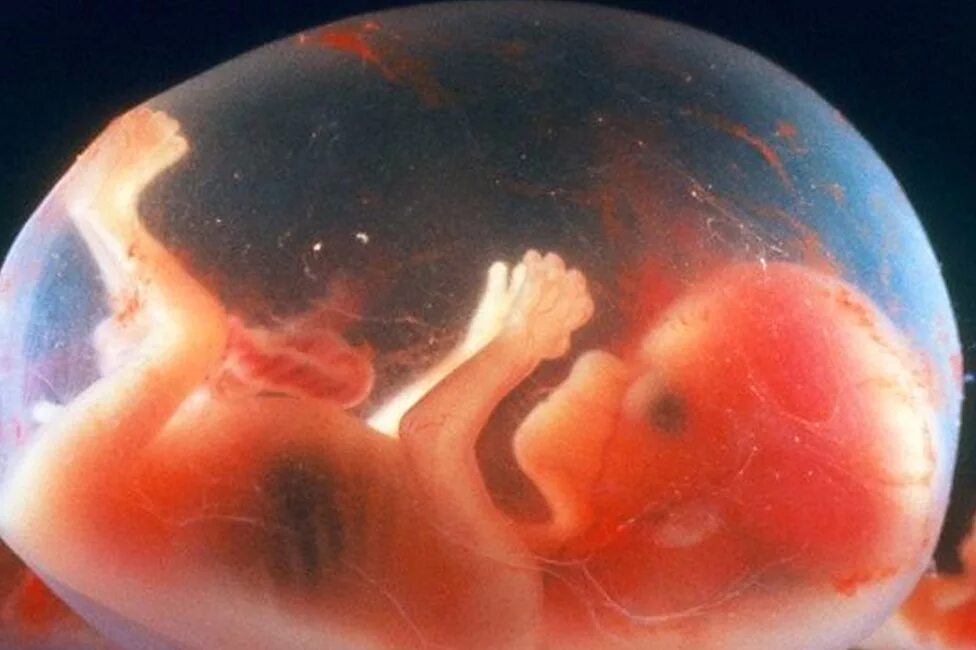

14 неделя ощущение